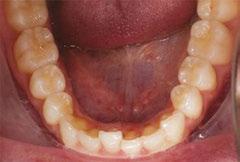

Upon closer examination, there were contributing factors that led to his discomfort. Stan had been a stomach/face sleeper for years. He also bit his nails since childhood, had a smoking habit from his youth, and he was prone to ear infections. He had moderate tongue and buccal ties, obligate mouth breathing, aggravated by a deviated septum, narrow nares, low tongue resting posture, an anterior open bite, a lower jaw that deviated upon opening, and bouts of acid reflux.

When the tongue rests in the palate, it impacts facial development especially for children who are still growing. An adult, for example, like our friend Stan, the progress made is gradual but more likely to last a lifetime. Generally, therapy starts out once a week for about 2-3 months. Then therapy progresses to every other week for 2-3 months, and then changes to once a month for about 5 months for the rest of the year. The exercises are done a minimum of 2 times everyday. These exercises are designed to strengthen and tone the orofacial muscles, building brand new neuromuscular function. When the muscles of the face are well developed, it may favorably impact appearance and the overall integrity of the facial structures. The muscles of the face also include the tongue, lips, cheeks and neck. Although the therapy program is typically only a year, Stan really liked how good he felt and decided to continue with some of the exercises to this day. From the photos you can see how much the program has impacted his health and well-being.

During his therapy, there was a discussion about the possible benefits he may receive from having his jaws expanded, making more room for his tongue, then to be followed by a tongue and buccal frenums release. His intermolar width is 34 mm, and his intercanine width is 25 mm. I feel any expansion has a potential benefit.

To document any initial assessment, the midpoint of therapy, and when therapy has ended, it is important to take detailed photos, videos, plus full measurements of the face and teeth. This makes it possible to compare results while showing that your therapy works based on the evidence you gathered before, during, and after treatment.

Figure 6: No room for his tongue

Figure 4: 7 years later on April 10, 2024. Anterior open bite closed a bit

Figure 2: Initial assessment on December 15, 2016 (top left). Later September 20, 2017, his anterior openbite widened (top right)